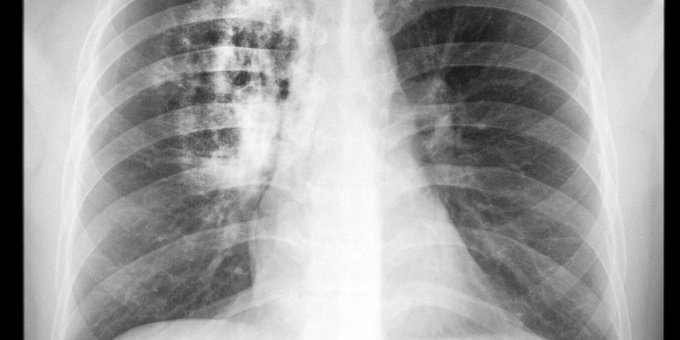

El trasplante de pulmón reemplaza uno o ambos pulmones enfermos por unos sanos del donante. ¿Qué afecciones hacen necesario un trasplante de pulmón? Eso y más aquí